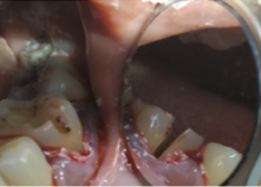

Placement of PRF Membrane